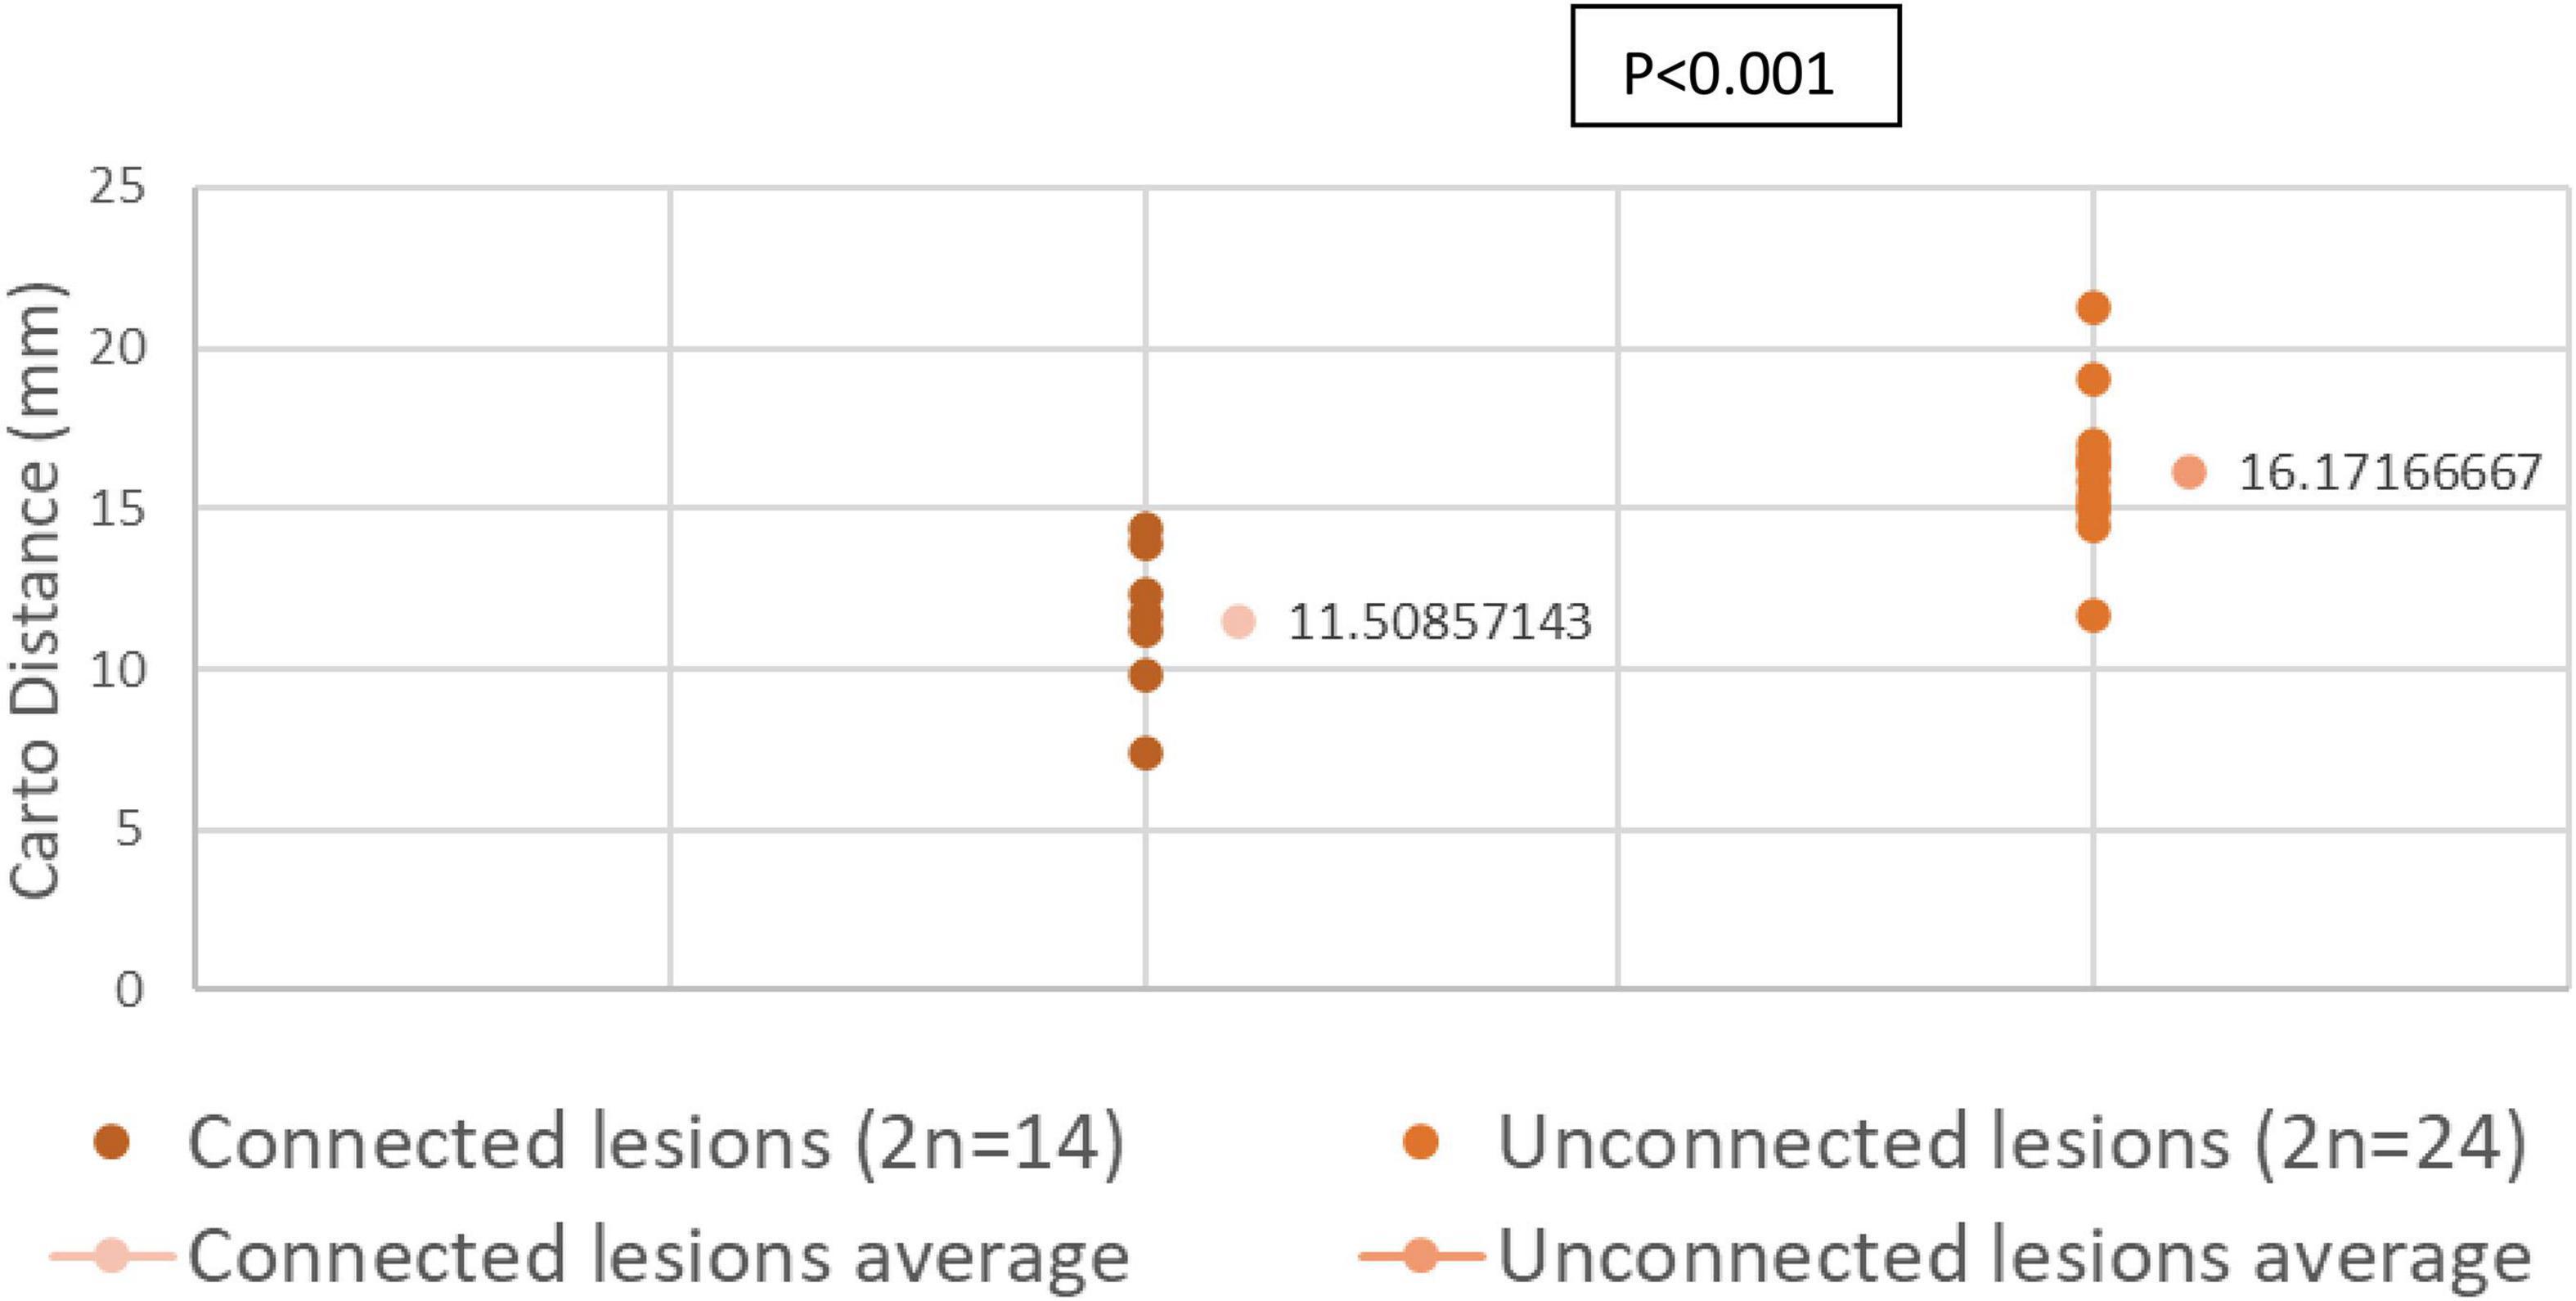

b- Distances Measured by EAM in Connected and Unconnected Lesions

We compared the distance across the endocardial surface between various paired lesions as measured by EAM. Connected paired lesions had an interlesion distance of 11.03 ± 0.92 mm. Unconnected paired lesions had an interlesion distance of 16.17 ± 0.68 mm (p < 0.001).

Distribution of interlesion distance in both connected and unconnected lesions are shown in Figure 5.